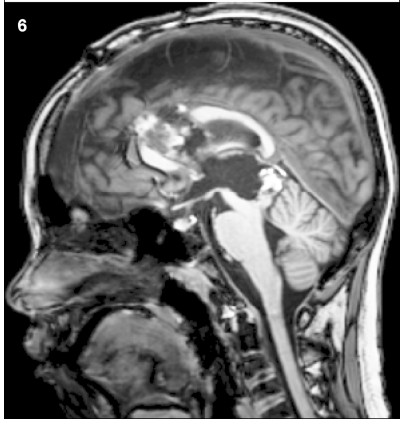

1.3 Treatment procedure The patient underwent frontal lobe and longitudinal craniotomy via a transcallosal-interforniceal approach. The elongated thalamic intermediate block could be seen. The tumor was noted to have various heterogeneous components,as well as remote hemorrhage with integrated tumor capsule,and was completely removed piece by piece. The patient had a seemingly satisfactory subsequent recovery,except for slight oculomotor abnormality and short-term memory dysfunction relieved within 2 weeks. Postoperative CT scan and MR imaging revealed total resection of the mass (Figure 5). Adjuvant cisplatin-based chemotherapy (5 days per cycle) was commenced at the 2nd week after operation. The patient’s serum tumor marker level declined to normal 1 week after chemotherapy,and synchronous MR imaging showed little hemorrhagic necrotic signal (Figure 6). Diffusiontensor imaging described partial destruction of the nerve fasciculus along the corpus callosum and integrated framework of the left fornix (Figure 7). The patient returned to school as usual 2 months after the operation. Pathological examination revealed mixed germ cell tumor (Figures 8a and 8b).

Figure 5 MRI showed that the tumor was totally removed with a satisfied result in magnetic resonance imaging findings in the 10th days after surgery.

Figure 6 MRI showed that a small amount of hemorrhage and necrosis were observed in the tumor area one week after chemotherapy in MRI findings.